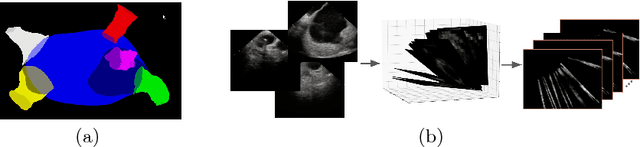

Abstract:Using catheter ablation to treat atrial fibrillation increasingly relies on intracardiac echocardiography (ICE) for an anatomical delineation of the left atrium and the pulmonary veins that enter the atrium. However, it is a challenge to build an automatic contouring algorithm because ICE is noisy and provides only a limited 2D view of the 3D anatomy. This work provides the first automatic solution to segment the left atrium and the pulmonary veins from ICE. In this solution, we demonstrate the benefit of building a cross-modality framework that can leverage a database of diagnostic images to supplement the less available interventional images. To this end, we develop a novel deep neural network approach that uses the (i) 3D geometrical information provided by a position sensor embedded in the ICE catheter and the (ii) 3D image appearance information from a set of computed tomography cardiac volumes. We evaluate the proposed approach over 11,000 ICE images collected from 150 clinical patients. Experimental results show that our model is significantly better than a direct 2D image-to-image deep neural network segmentation, especially for less-observed structures.